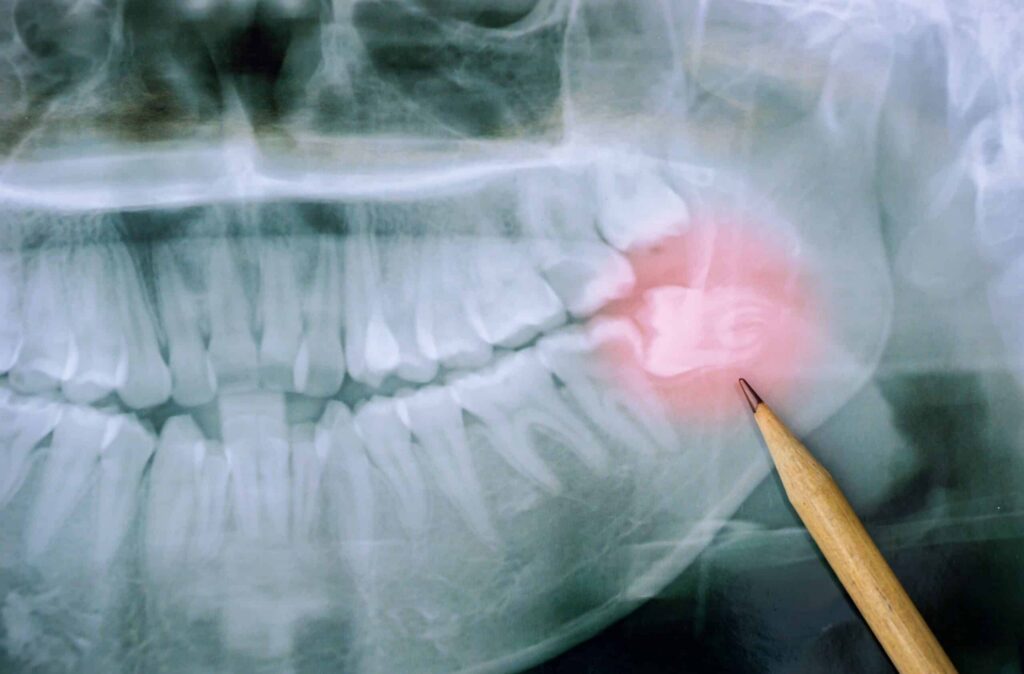

X-ray image highlighting impacted wisdom teeth with a pencil pointing to the affected area, illustrating common dental issues related to third molars.

One common issue with wisdom teeth is that our modern jaws are often too small to accommodate them comfortably. This can lead to impacted wisdom teeth, which don’t fully emerge or grow at odd angles. These impacted teeth can cause pain, swelling, and infection if left untreated. In such cases, a visit to your dentist is essential to evaluate whether removal is necessary.